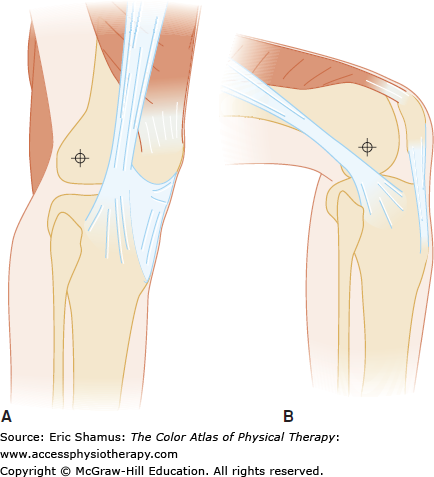

Answer with rationale: A. Ober Test, Noble Compression Test, Creak Test. All three of these test are considered positive if pain or crepitus is reproduced. Pain reproduced through these tests supports a diagnosis of iliotibial band syndrome.